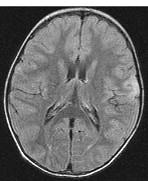

女,3岁,头痛、呕吐1周,请结合MRI图像,选择最可能的诊断是()A.脑膜炎B.硬膜下出血C.脑转移瘤D.脑梗死E.脑脓肿

问题 女,3岁,头痛、呕吐1周,请结合MRI图像,选择最可能的诊断是()

选项 A.脑膜炎 B.硬膜下出血 C.脑转移瘤 D.脑梗死 E.脑脓肿

答案 A